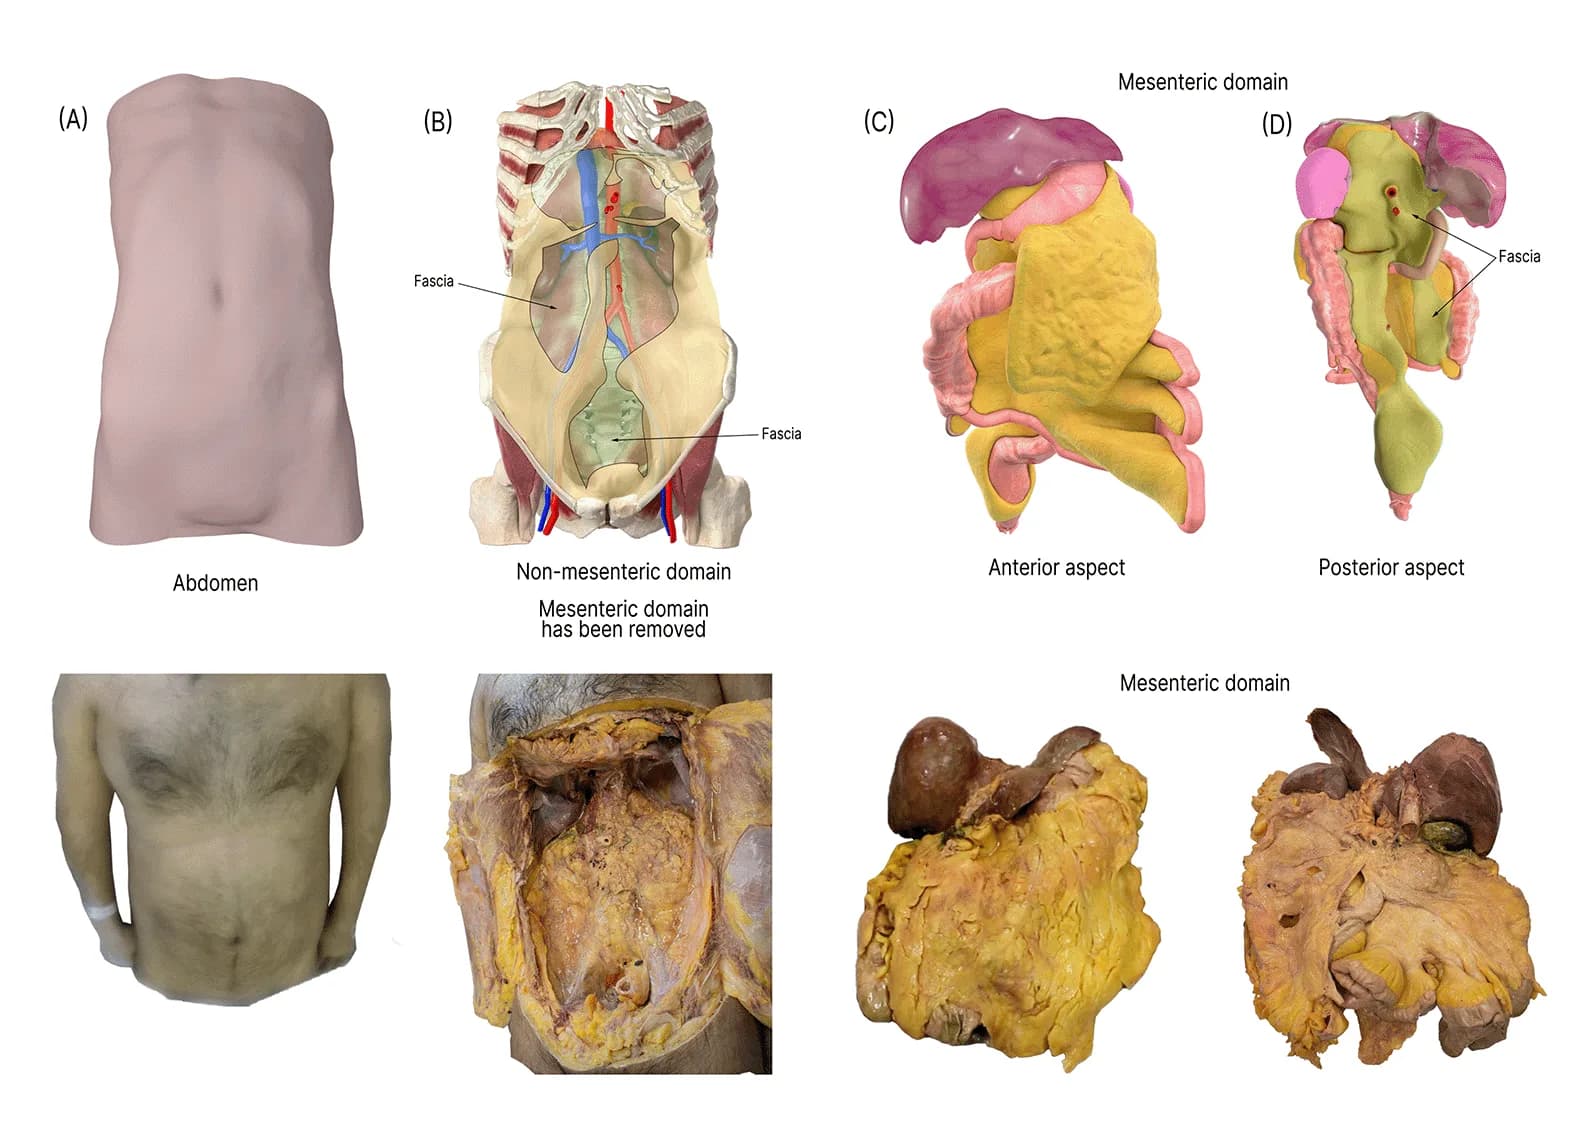

Mesentery: Advanced Anatomical Research is a long term, multidisciplinary research programme focused on redefining the understanding of mesenteric anatomy, development, and disease. The research has been ongoing for over 14 years, evolving alongside advances in surgical practice, imaging technology, and anatomical science.

Following embryological analysis, the research expanded into cadaveric dissection, allowing direct anatomical validation of developmental concepts. Cadaver studies provided high resolution insight into structural continuity, fascial planes, and anatomical relationships not fully appreciable through imaging alone.

The next major research phase incorporated medical imaging, particularly CT scans, to correlate anatomical findings with radiological appearances. This allowed anatomical continuity and structural relationships to be identified non invasively across large patient populations.

Imaging analysis strengthened the translational value of the research, making findings applicable beyond the operating theatre and dissection room. It also facilitated comparison between normal anatomy and pathological change, reinforcing the clinical relevance of the work.

Understanding disease through the lens of a consistently defined mesenteric structure allowed for clearer interpretation of surgical findings and helped standardise anatomical language across clinical disciplines.

Findings from the research have been used to support education at multiple levels, including medical students, surgical trainees, and consultants. Material derived from this programme has been adapted for teaching, presentation, and professional discussion, ensuring that new anatomical insights are translated into clinical understanding.